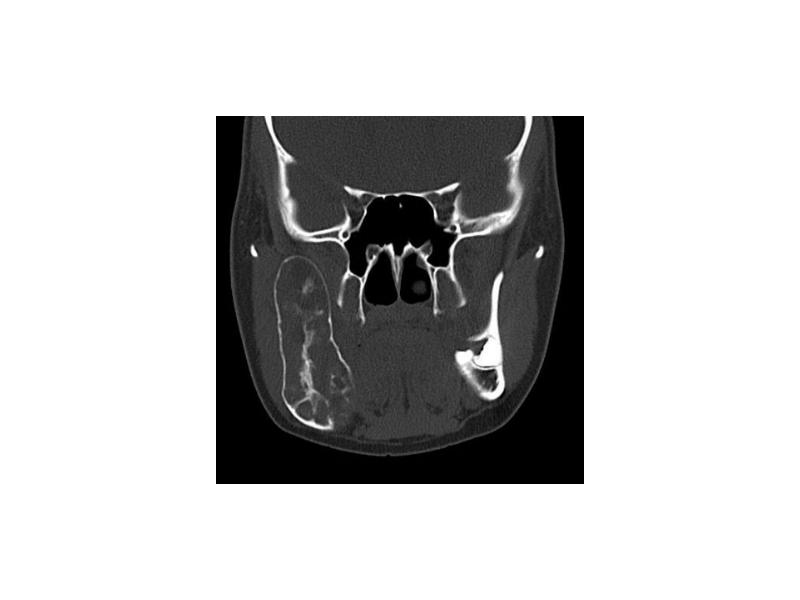

- 10. Амелобластома Доброкачественная опухоль с медленным, местнодеструирующим ростом В 80% тело нижней

- 11. Макроскопическая картина Пораженная челюсть веретенообразно утолщена ("вздутие"), при разрушении кортикальной пластинки